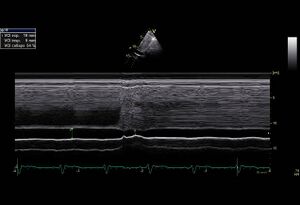

Respiratory failure

In a normal RA pressure collapses the VCI in 80% of the cases, >40% (measured at inmonding hepatic vein). ±40% collapse VCI corresponds to a pressure of 8 - 10mmHg . At a collapse of 60-70%, the pressure in the VCI most often 2- 4mmHg. At a collapse <40%, the VCI pressure > 10mmHg (85%). When dilated , not collapsing VCI can pressure 20 - 25mmHg are .

Echocardiographic view

SubcostaalVCI.png VCImmode01.jpg

Subcostale view M-mode collapse VCI